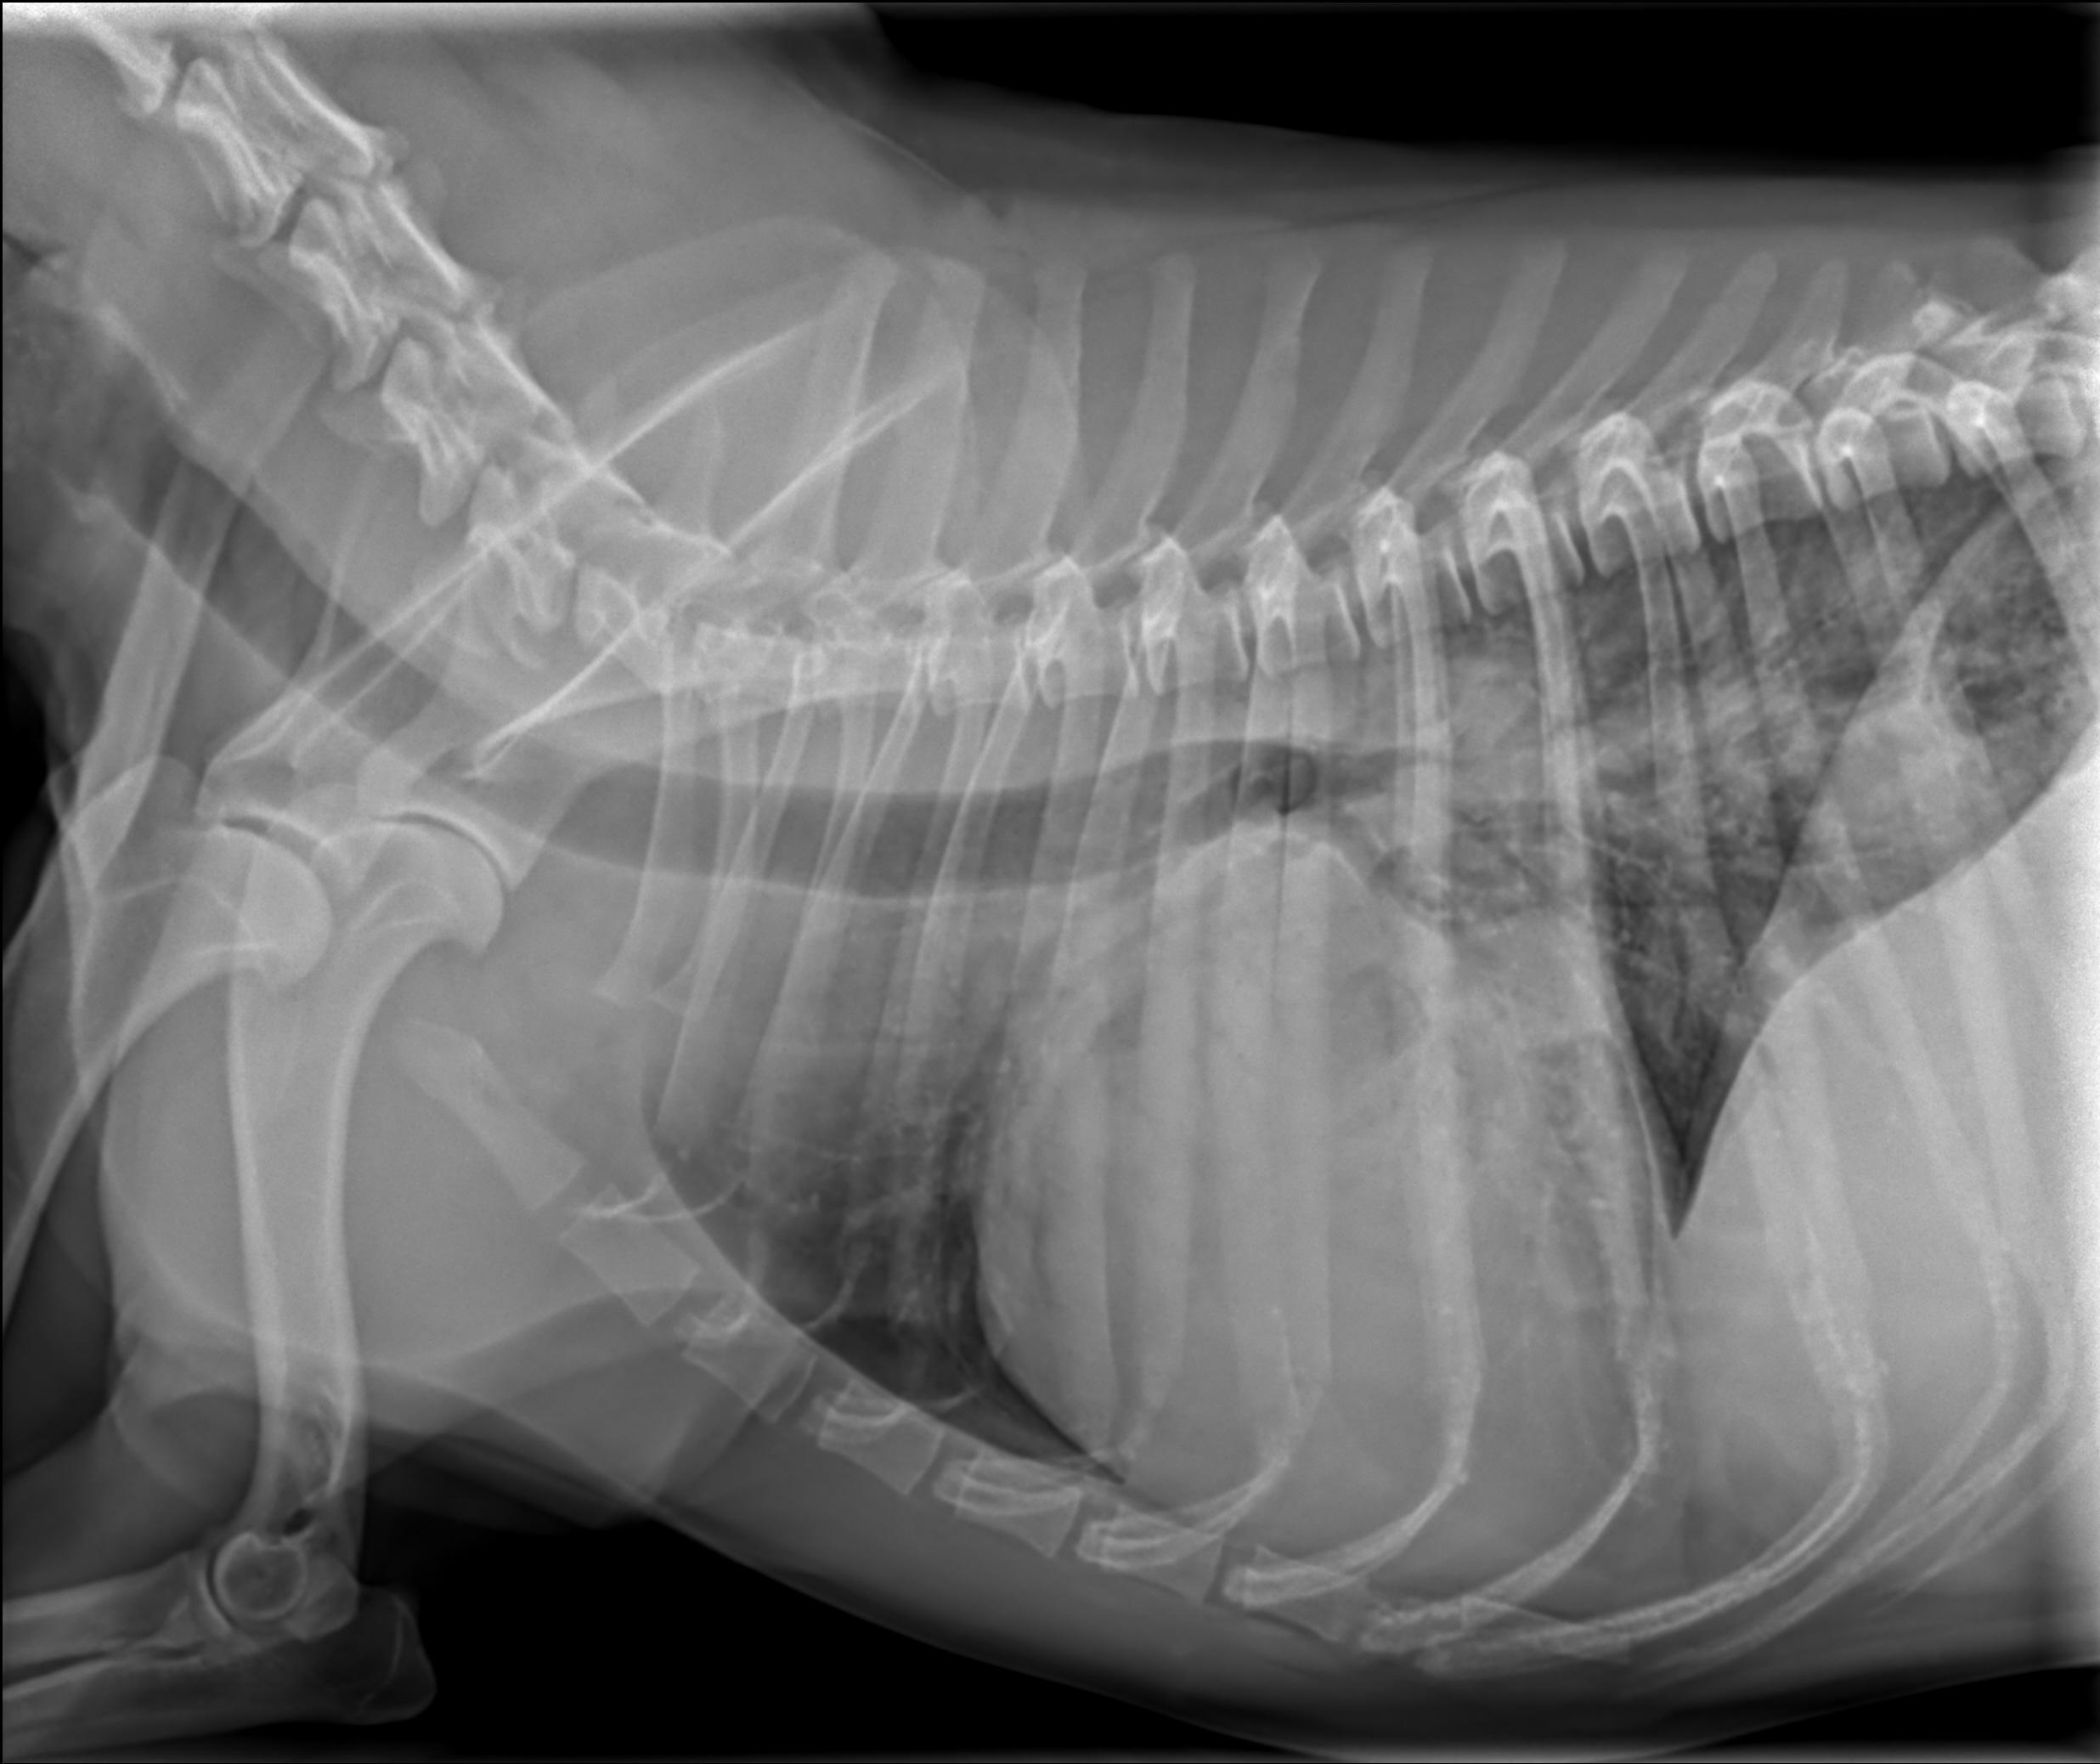

Kadar veterinar pri tem posumi na bolezen srca, je potreben celosten pregled kardiovaskularnega sistema, ki ga opravi veterinar – kardiolog. Ta večinoma obsega klinični pregled, ultrazvok srca, EKG in ob sumu na dekompenzacijo rentgen pljuč. To nam omogoči postavitev natančne diagnoze, ki je ključnega pomena za uspešnost terapije in dolgoročno prognozo.

Pri tej okvari srca gre za primarno izgubo moči srčne mišice. Najpogosteje so prizadete večje pasme, od manjših pa nekateri španjeli. Za bolezen je značilna dolga, večinoma več let trajajoča latentna faza, v kateri je možno bolezen odkriti le z natančnim kardiološkim pregledom. V končnem stadiju bolezni pa pride tudi do dekompenzacije z zastajanjem tekočine v pljučih in trebušni votlini, motnjami srčnega ritma, izgubo telesne teže in mišične mase. Žival pri tem težko diha, se hitro utrudi, lahko občasno izgubi zavest; nekateri psi pa brez predhodnih bolezenskih znakov nenadoma poginejo. Pravočasno prepoznavanje bolezni je pomembno tako z vidika zdravljenja kakor tudi zaradi izločitve prizadetih živali iz vzreje. V večini primerov se z ustreznim zdravljenjem precej podaljša dolžina in kakovost življenja prizadetih psov; nekateri tipi kardiomiopatije pa so celo ozdravljivi.

Omenjene bolezni so le ene od tistih, s katerimi se srečujemo veterinarski kardiologi; seveda pa je srčnih obolenj še veliko več. Za uspešnost zdravljenja je največjega pomena natančna diagnoza. Te si v današnji veterinarski kardiologiji, ki v mnogih stvareh sledi humani medicini, ne moremo več predstavljati brez specialističnih preiskav. Sem sodi na prvem mestu ultrazvočna preiskava srca, ki je za postavitev diagnoze nepogrešljiva. Za celostno sliko obolenja pa večinoma potrebujemo še dodatne preiskave, kot so rentgensko slikanje pljuč, elektro kardiološka preiskava srčnega ritma, merjenje krvnega tlaka. Terapijo je nato potrebno natančno prilagoditi potrebam posameznega pacienta, saj se na zdravila ne odzovejo vsi enako. Tu je izjemnega pomena tesno sodelovanje in zaupanje med skrbnikom psa in izbranim veterinarjem – kardiologom. Le na tak način si zagotovimo optimalno kontrolo bolezni ter zadovoljstvo vseh: živali, njihovih skrbnikov ter ne nazadnje nas, kardiologov.